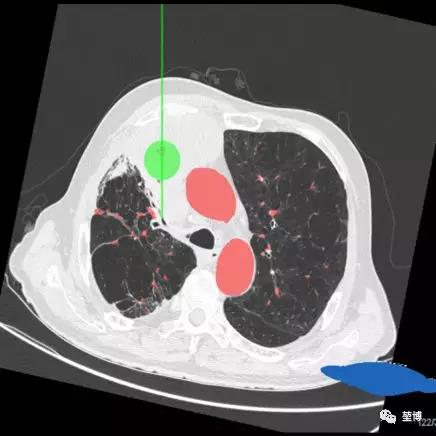

术前路径规划

一、气道内消融路径规划

右上叶RB1

RB1的b支

RB1b支的左下亚支

二、气道外消融路径规划

POE穿刺点位于RB3

建立隧道直达病灶中心